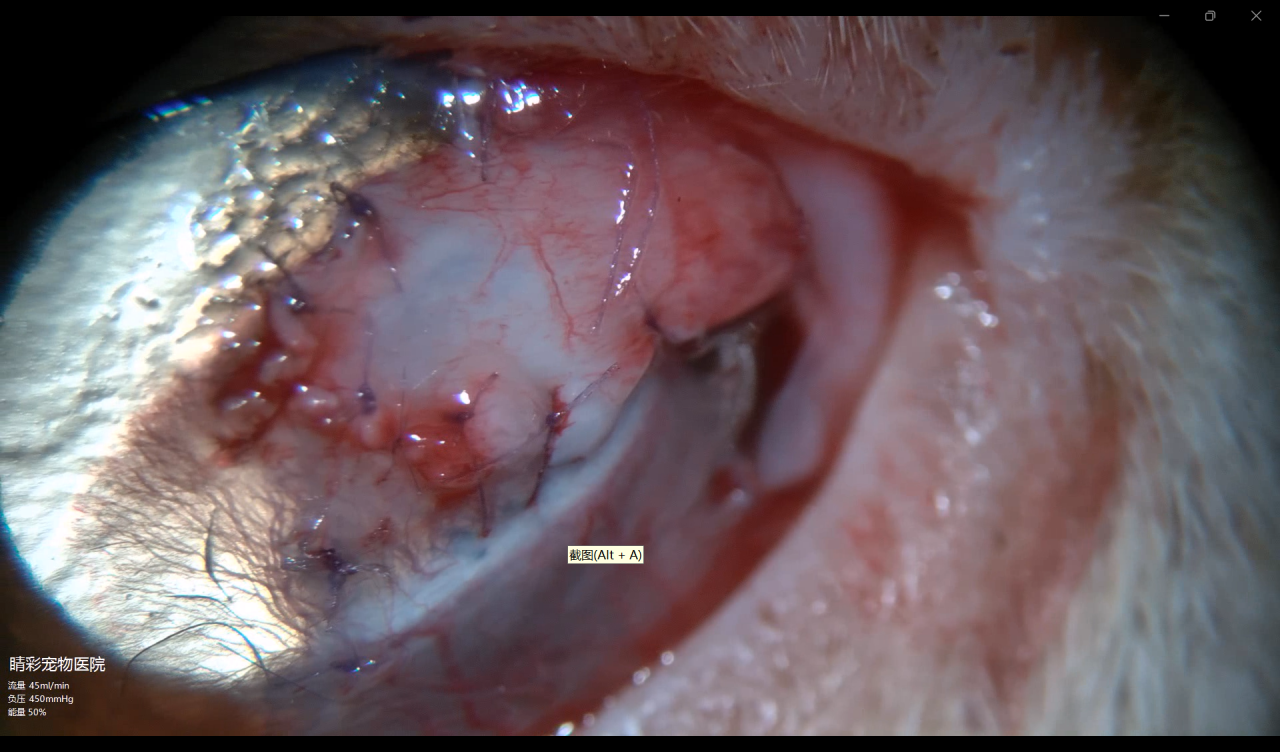

4.3、十四天拆线复查:

复查中发现左眼角结膜瓣,覆盖在sis补片部分的角膜瓣出现退缩状况,术中穿孔部位暴露,后弹力层膨出,拆线当天即出现角膜穿孔,房水渗出。(图4-3)

图4-3 拆线当天发现角膜瓣退缩,

术中穿孔位置暴露

4.4、二次手术

对穿孔点周围角膜进行清创、热成型,并进行sis补片加结膜瓣修补(图1-4)

图4-4 结膜瓣术中